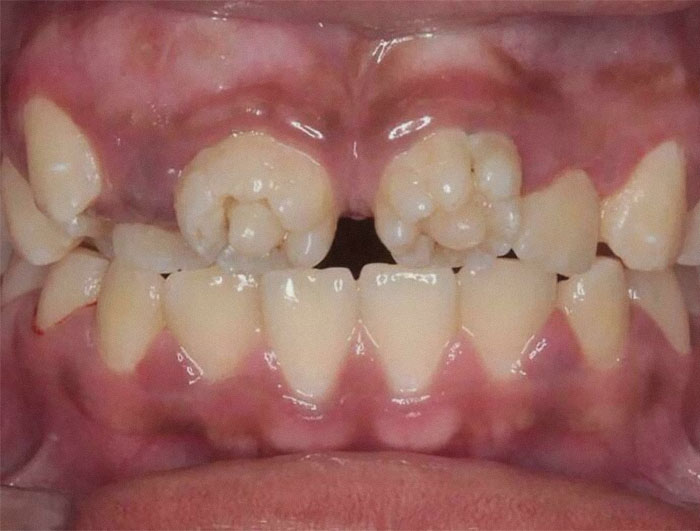

#19 These Are Mulberry Molars, Which Are Associated With Congenital Syphilis

Image credits: mriTecha